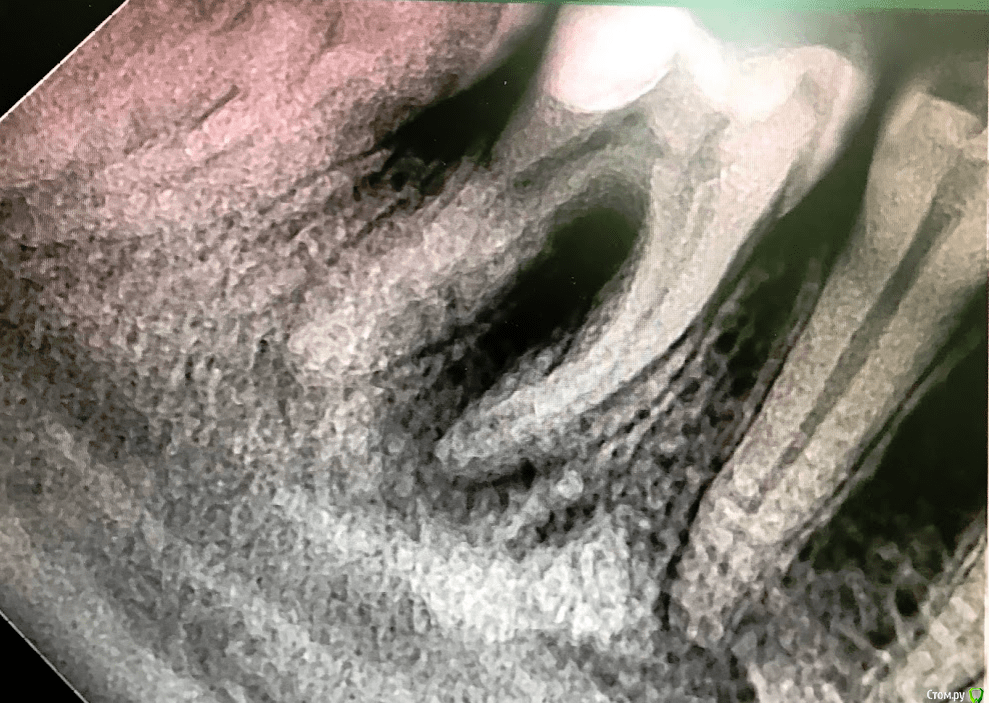

Евгений Семченок Опубликовано 26 мая, 2019 Поделиться Опубликовано 26 мая, 2019 26.02.16 вылечила 46 зуб, нерв не удаляли,обработали полость, поставили постоянную пломбу. 26.05.19 зуб начал болеть, обратилась повторно к другому врачу. Вскрыли пломбу и сказали, что воспалительный процесс начался из за неправильного лечения при первом обращении с этим зубом. Якобы при жалобах такого характера и таком снимке удаление нервов нужно проводить сразу и в этом случае зуб бы не воспалился и не потребовалось бы повторного лечения. Прошу специалистов помочь разобраться. Фото со снимками при первом и повторном обращении приложила, так же во вложении фото из карточки с жалобами и диагнозом при первом посещении. Ссылка на комментарий